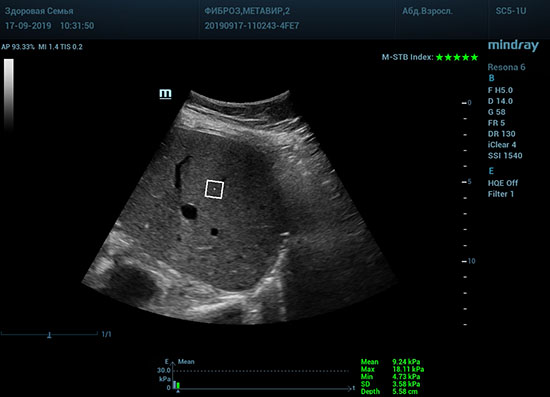

Что может дать ультразвуковое исследование печени помимо образований, гепатомегалии и цирроза? Диагностические системы, оснащенные функцией STQ (SoundTouchQuantification) имеют возможность регистрировать сдвиговые волны в паренхиме печени и оценить её эластичность. Такие возможности есть у систем серии Resona 6 и Resona 7 компании Mindray.

Определение плотности печени. Не ошибся ли оператор при измерении эластических свойств печени? Для оценки критериев качества предусмотрен индекс MBT, который покажет насколько «твердой» была рука оператора и двигалась ли печень. При MBT 5* рука тверда и показатели достоверны. Для оценки качества результатов используется IQR индекс, отображающий колебания показателей в точке измерения при расчете медианы. Показатели при IQR <30% считаются приемлемыми. Техника сканирования через межреберные промежутки требует размещение окна интереса на несколько сантиметром ниже капсулы, для исключения эффекта реверберации. Установка ROI на паренхиму без захвата сосудов, для исключения погрешностей измерения.

Стадия фиброза определяется по системе METAVIR Staging, построенной на данных биопсии и сопоставлении с данными эластографии. Своевременная диагностика фиброза, и начало его лечения, залог благоприятного исхода заболевания.